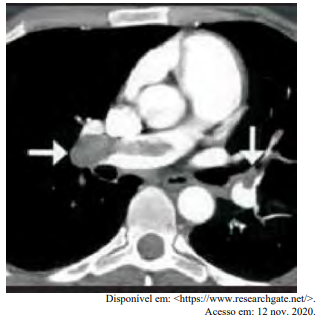

Certa idosa de 70 anos de idade é levada ao consultório médico por familiares, com relato de dor no peito há oito horas. Quanto a comorbidades, ela apresenta hipertensão arterial sistêmica e insuficiência cardíaca. Estava em casa assistindo à televisão quando sentiu uma dor súbita no peito, de moderada intensidade, que piora com a inspiração profunda, irradiando para o dorso, em queimação e associada a palpitações e a falta de ar importante, mesmo em repouso. Nega náuseas e sudorese. Não melhora após tomar dipirona. A dor continua da mesma forma, mas o que levou os familiares a procurarem atendimento foi a piora da falta de ar. Faz uso de losartana, atenolol, espironolactona, AAS e sinvastatina. Nega etilismo e informa que tinha o hábito de tabagismo, mas parou há mais de 10 anos. Tem histórico anterior de cirurgia de artroplastia de quadril há mais de um ano. Tem ficado muito tempo em repouso, assistindo à TV, principalmente depois da pandemia de Covid-19. Ao exame físico, constatam-se PA = 89 mmHg x 59 mmHg, FC = 125 bpm, FR = 27 ipm e SatO2 = 89% em ar ambiente. A paciente está afebril, em estado geral regular, lúcida, orientada e comunicativa. As auscultas pulmonar e cardíaca mostram-se sem alterações. Observam-se abdome inocente, membros inferiores com cacifo + discreto e simétrico, panturrilhas livres e pulsos preservados. A paciente realiza o eletrocardiograma e a tomografia de tórax, conforme representado nas imagens a seguir.

Com base nesse caso clínico, nos exames representados nas imagens e nos conhecimentos médicos correlatos, julgue o item a seguir.

O eletrocardiograma (ECG) apresenta um achado específico para tromboembolismo pulmonar (TEP).